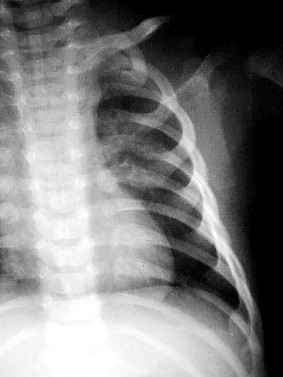

A newborn is diagnosed with congenital scoliosis secondary to a fully segmented hemivertebra at T8.

Which of the following is the most appropriate routine screening protocol to order next to evaluate for frequently associated anomalies?